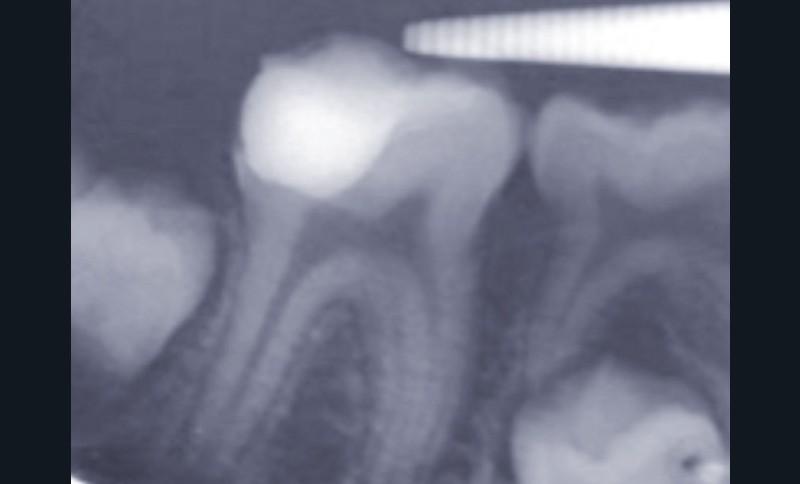

Restaurer sans tenon la dent dépulpée (fig. 4, 5, 6)

Selon les analyses de la littérature récente, la dent dépulpée n’est pas plus fragile que la dent pulpée. En revanche, les pertes de structure (a fortiori mésio-occluso-distale, lorsque les deux crêtes marginales sont perdues), et plus encore les tenons radiculaires, sont les éléments qui fragilisent la dent dépulpée. Ainsi, aussi souvent que possible, la dent dépulpée sera reconstituée sans tenon.

Lorsque la dent présente 4 parois résiduelles, une restauration en composite direct est indiquée. Pour 3 parois avec au moins une crête marginale, une restauration directe ou indirecte convient, si toutefois elles sont collées, car le collage augmente la résistance mécanique de l’organe dentaire résiduel. Pour 2 parois sans crêtes marginales, l’épaisseur des parois et la nature de la dent (les prémolaires étant plus fragiles que les molaires) vont permettre d’arbitrer entre reconstitution partielle collée ou endocouronne : le sertissage de la dent résiduelle ainsi obtenu la renforce considérablement. Le recours au tenon radiculaire sera donc réservé aux situations de délabrement très important, et il sera utilisé dans un but de rétention, et non pas dans un but de consolidation de l’organe dentaire.